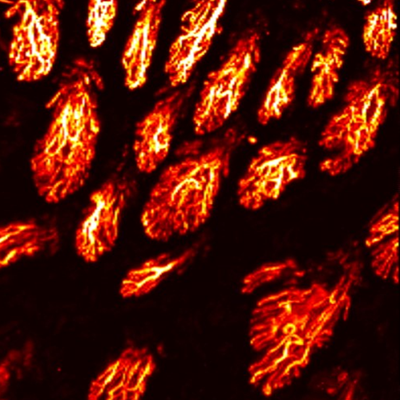

Layer by layer visualization of subdermal microvessels and pigments

Endogenous hemoglobin and melanin allow for daily monitoring

MAP

Cross sectional view

Surface(Depth) view